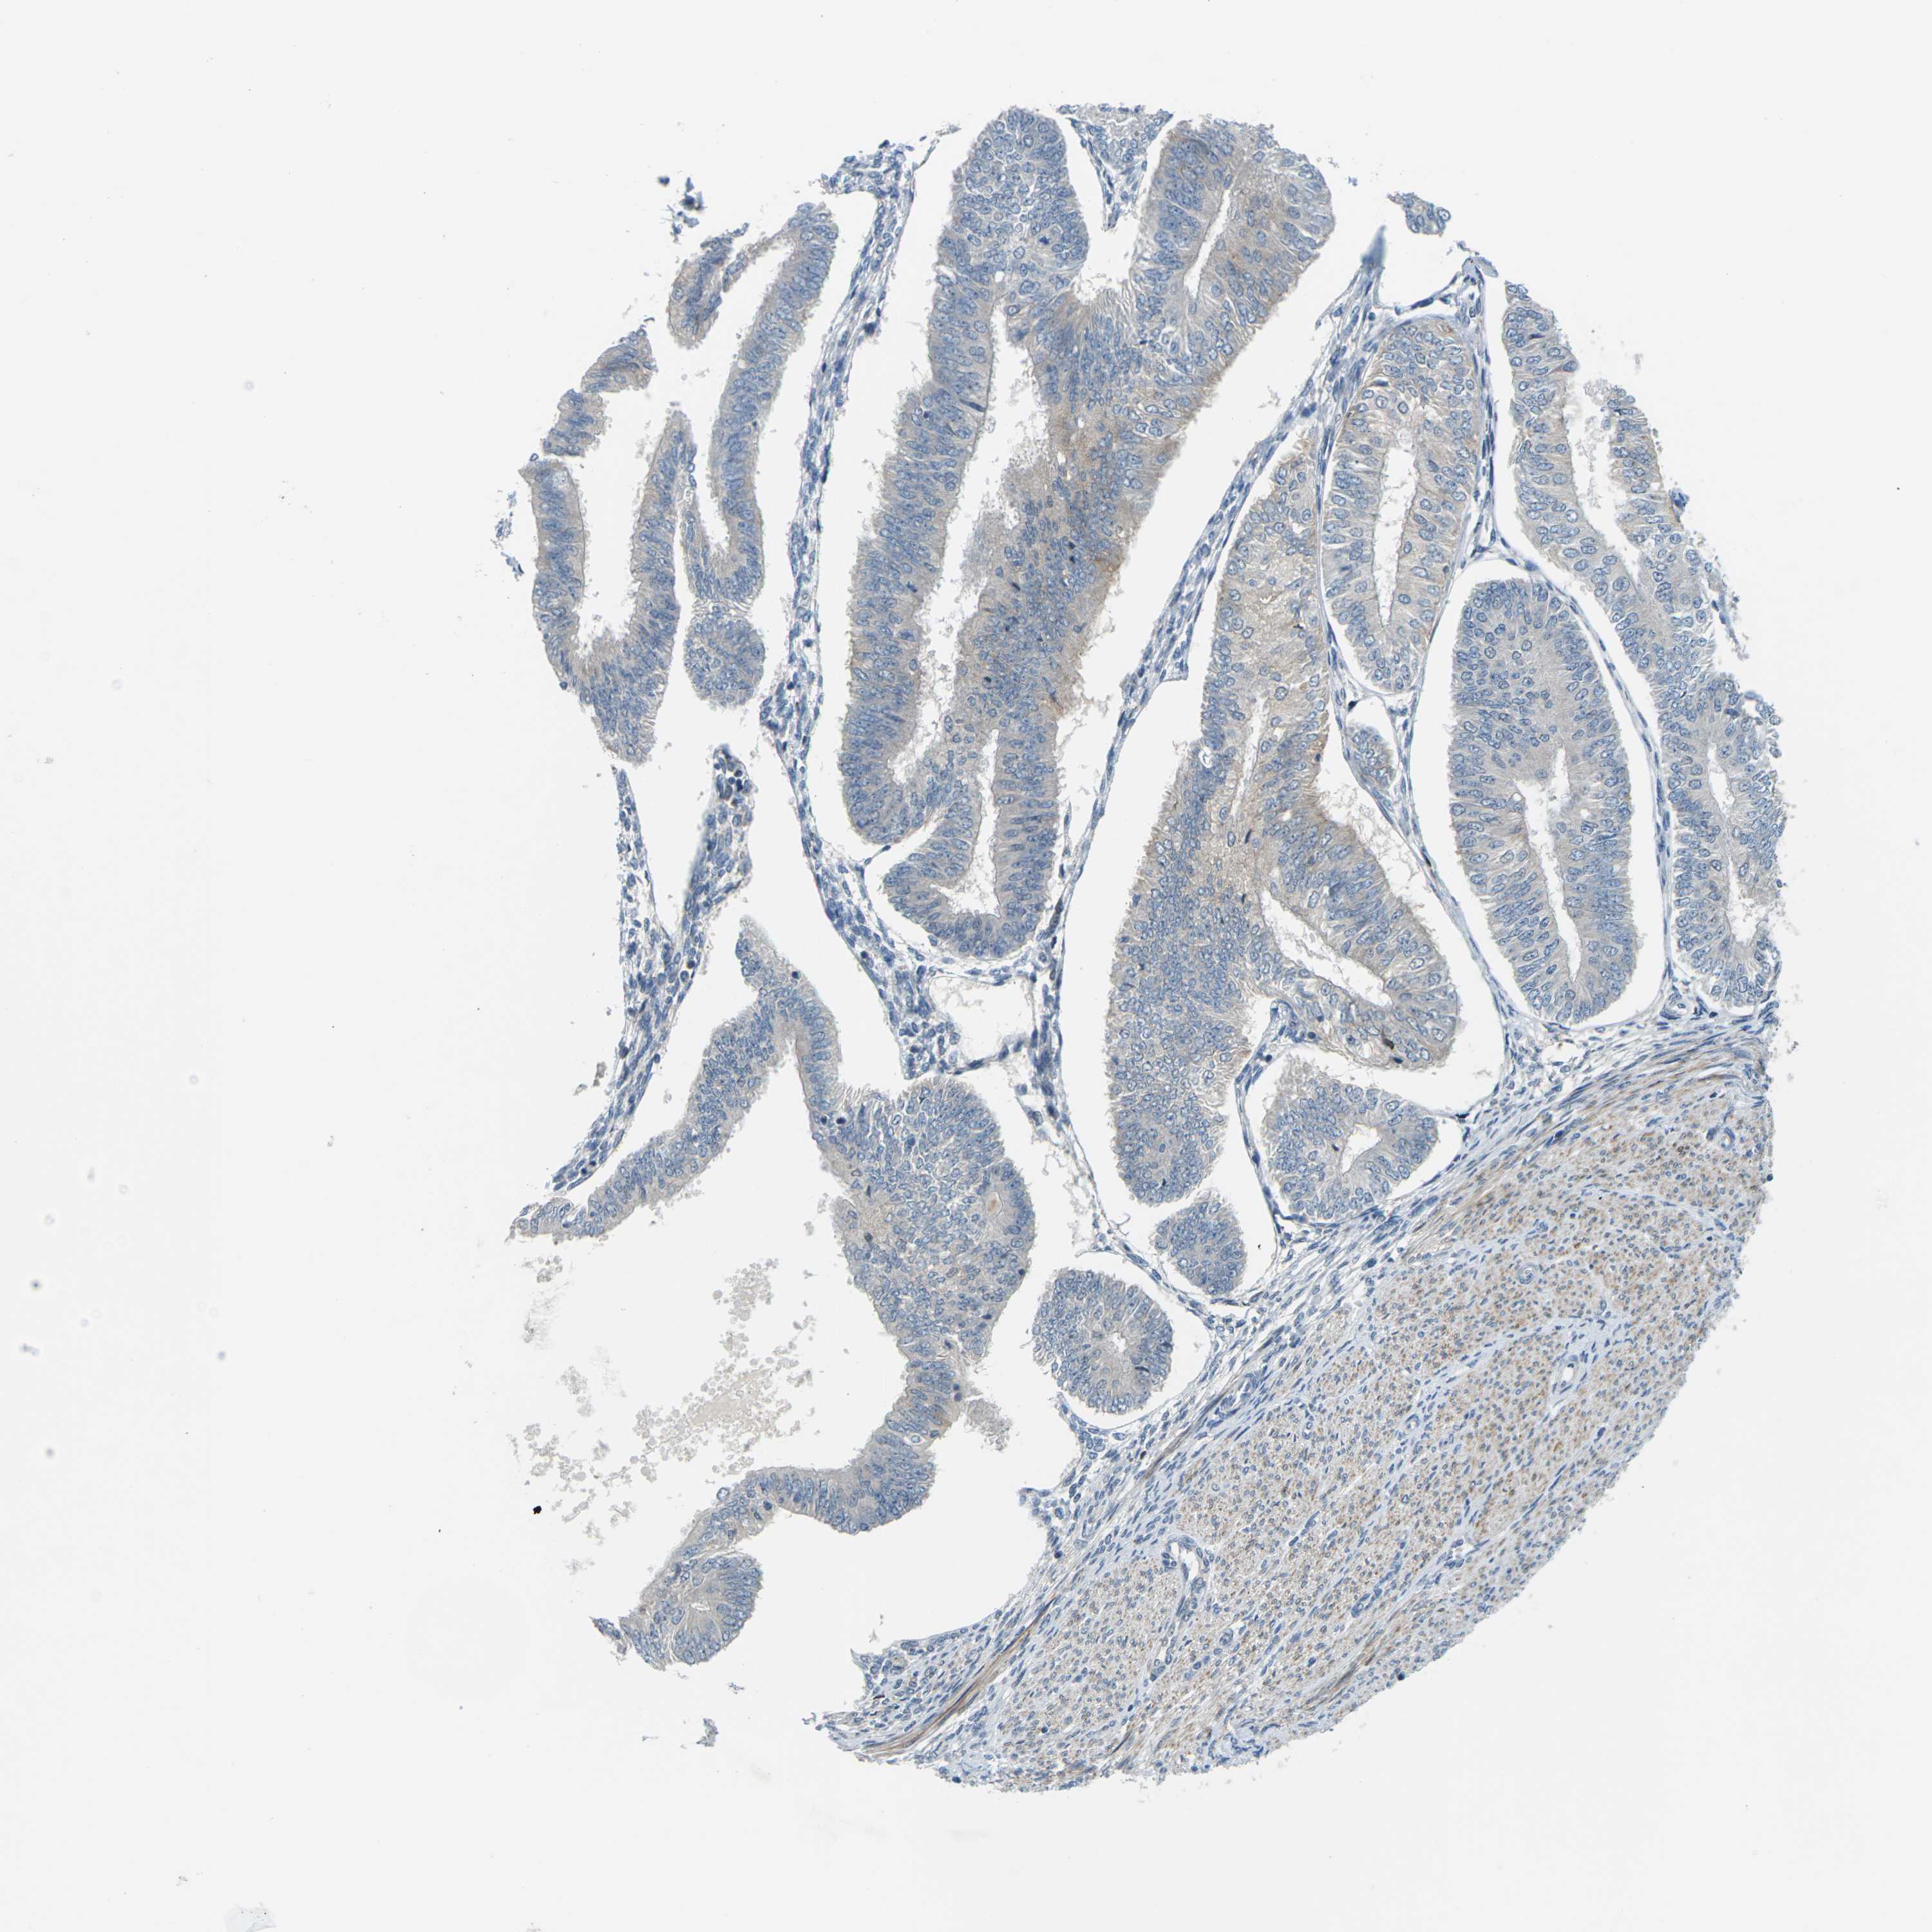

ENDOMETRIAL CANCER - Protein expressioni

A mouse-over function shows sample information and annotation data. Click on an image to view it in a full screen mode. Samples can be filtered based on level of antibody staining by selecting one or several of the following categories: high, medium, low and not detected. The assay and annotation is described here.

Note that samples used for immunohistochemistry by the Human Protein Atlas do not correspond to samples in the TCGA dataset.

Antibody stainingi

Antibody staining in the annotated cell types in the current human tissue is reported as not detected, low, medium, or high, based on conventional immunohistochemistry profiling in selected tissues. This score is based on the combination of the staining intensity and fraction of stained cells.

Each image is clickable and will lead to virtual microscopy that enables deeper exploration of all samples and also displays staining intensity scores, fraction scores and subcellular localization as well as patient and tissue information for each sample.

Antibody HPA014353

Antibody HPA014736

Staining

High

Medium

Low

Not detected

Intensity

Strong

Moderate

Weak

Negative

Quantity

>75%

75%-25%

<25%

None

Location

Nuclear

Cytoplasmic/membranous

Cytoplasmic/membranous,nuclear

Adenocarcinoma, NOS